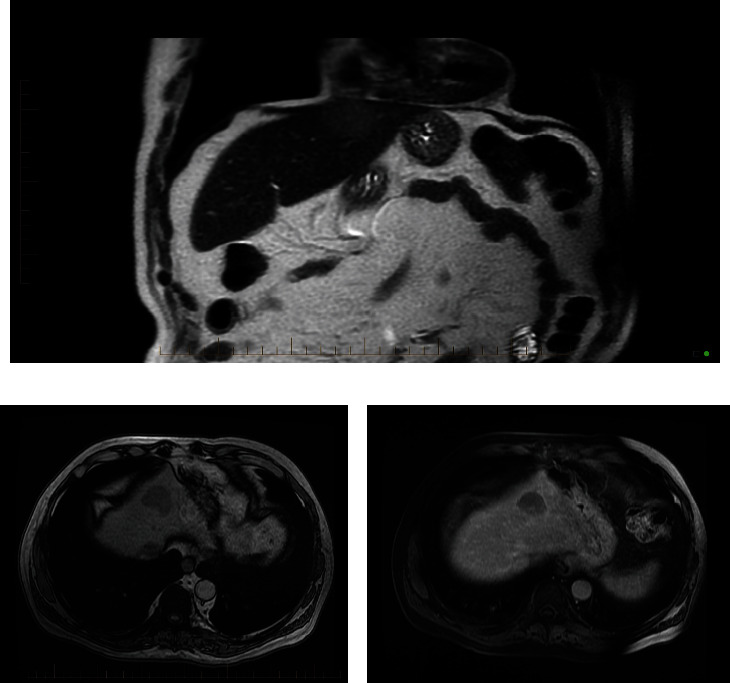

Prostate-specific membrane antigen positron emission tomography (PSMA PET) has been approved by the Food and Drug Administration (FDA) to identify prostate cancer in the setting of biochemical recurrence but can also identify other malignancies. 18F-PSMA PET has not been studied as a potential tool for hepatocellular carcinoma (HCC). We describe the case of a 76-year-old male with a rising prostate-specific antigen (PSA) after definitive prostate cancer treatment and no prior liver pathology who was incidentally found to have HCC on 18F-PSMA PET.

Abstract Image